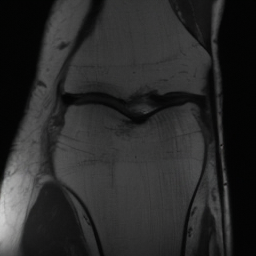

5.3 Out-of-Domain Generalisation

One way to test the generalization capability of the trained X-Diffusion is to test it on a completely different domain from an MRI dataset not seen during training. We report the single-slice results on NYU fastMRI [37, 82], a knee MRI dataset, using the X-Diffusion trained on the BRATS brain MRIs. The results are shown in Figure 9 and Table 2. It shows how successfully X-Diffusion is able to generate knee MRIs from a single image, despite not seeing knees at all in training. To qualitatively assess how realistic our generated 3D volumes were (produced from a single slice), we gave 20 generated examples alongside their real MRI counterparts to an expert orthopaedic surgeon. He was then asked to identify the real example from a given pair. The surgeon identified with certainty only 10 real knee MRIs out of 17, while could not decide on the remaining 3 of the 20 MRI pairs. This further validates the generated out-of-domain MRIs.